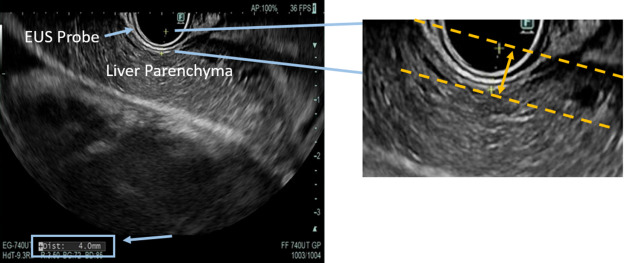

In Articles in Press: “EUS-guided liver palpation as a screening tool for advanced fibrosis and cirrhosis in patients with suspected metabolic dysfunction–associated steatotic liver disease: a pilot study" by Thomas J. Wang et al. giejournal.org/article/S0016-… Thomas Wang Raj Shah

In Articles in Press: “EUS-guided liver palpation as a screening tool for advanced fibrosis and cirrhosis in patients with suspected metabolic dysfunction–associated steatotic liver disease: a pilot study" by Thomas J. Wang et al. giejournal.org/article/S0016-…

<a href="/ThomasWangMD/">Thomas Wang</a> <a href="/Jarshah4/">Raj Shah</a>